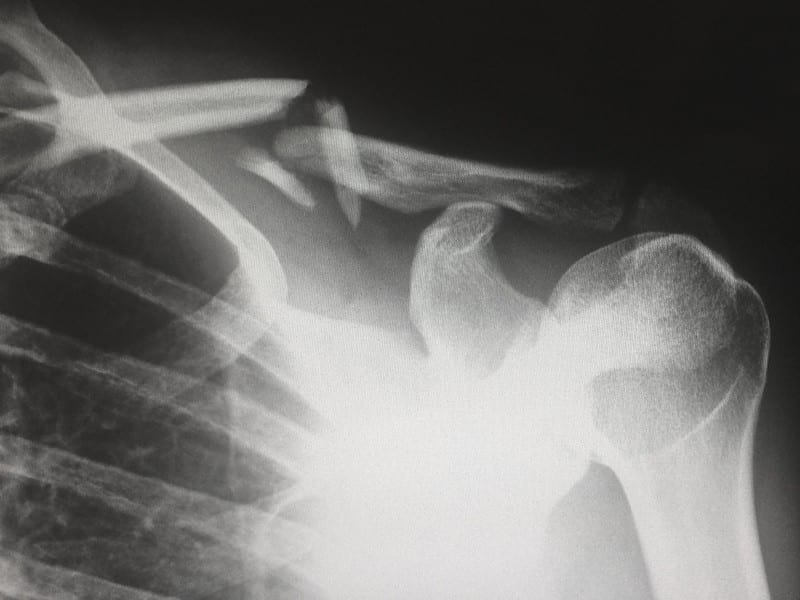

La spalla è l’articolazione più mobile e quindi più complessa del nostro corpo. È composta da tre ossa: omero, clavicola e scapola che sono legate tra loro mediante muscoli, tendini e legamenti, formando tra loro diverse articolazioni che lavorano in stretta sinergia. Tutte queste strutture devono consentire da un lato una grande mobilità, ma allo stesso tempo devono garantire la massima stabilità durante tutti i movimenti della spalla. Per ogni movimento del braccio vengono coinvolti numerosi muscoli che si attivano e disattivano secondo delle precise “catene cinetiche”. Basti pensare che quando alziamo il braccio il primo muscolo che si attiva è addirittura il gluteo, poi in successione i muscoli lombo pelvici e, solo in fine, quelli propriamente della scapola e della spalla.

Frequentemente si pensa che le lesioni alla spalla siano di origine traumatica: una caduta, un incidente o dei microtraumi ripetuti come avviene in alcuni sport tipo il tennis o il golf, possono provocare delle rotture sia di tendini e legamenti, sia delle parti ossee. Spesso però la causa originale risiede in una discinesia: una alterazione del normale movimento della spalla a causa di compensi muscolari, di un dolore alla spalla non trattato o trattato male, di un vecchio trauma sportivo. Questi movimenti sbagliati, ripetuti nel tempo, vanno a deteriorare sia le strutture tendinee della cuffia dei rotatori che le componenti ossee.

Per riparare alcune lesioni è necessario ricorrere a un intervento chirurgico in “artroscopia”. Per altre lesioni invece si deve ricorrere a delle piccole incisioni a “cielo aperto”. Quando invece l’articolazione della spalla è danneggiata in modo importante e provoca dolore costante è necessario fare una protesi. A seconda del tipo di lesioni e danni alle strutture, l’ortopedico opterà per una protesi anatomica della spalla o per una protesi inversa. L’importante, in tutti i casi, è rivolgersi a un ortopedico veramente esperto di spalla, che sappia effettuare al meglio la valutazione del danno e naturalmente sappia eseguire l’intervento secondo le ultime tecniche chirurgiche.